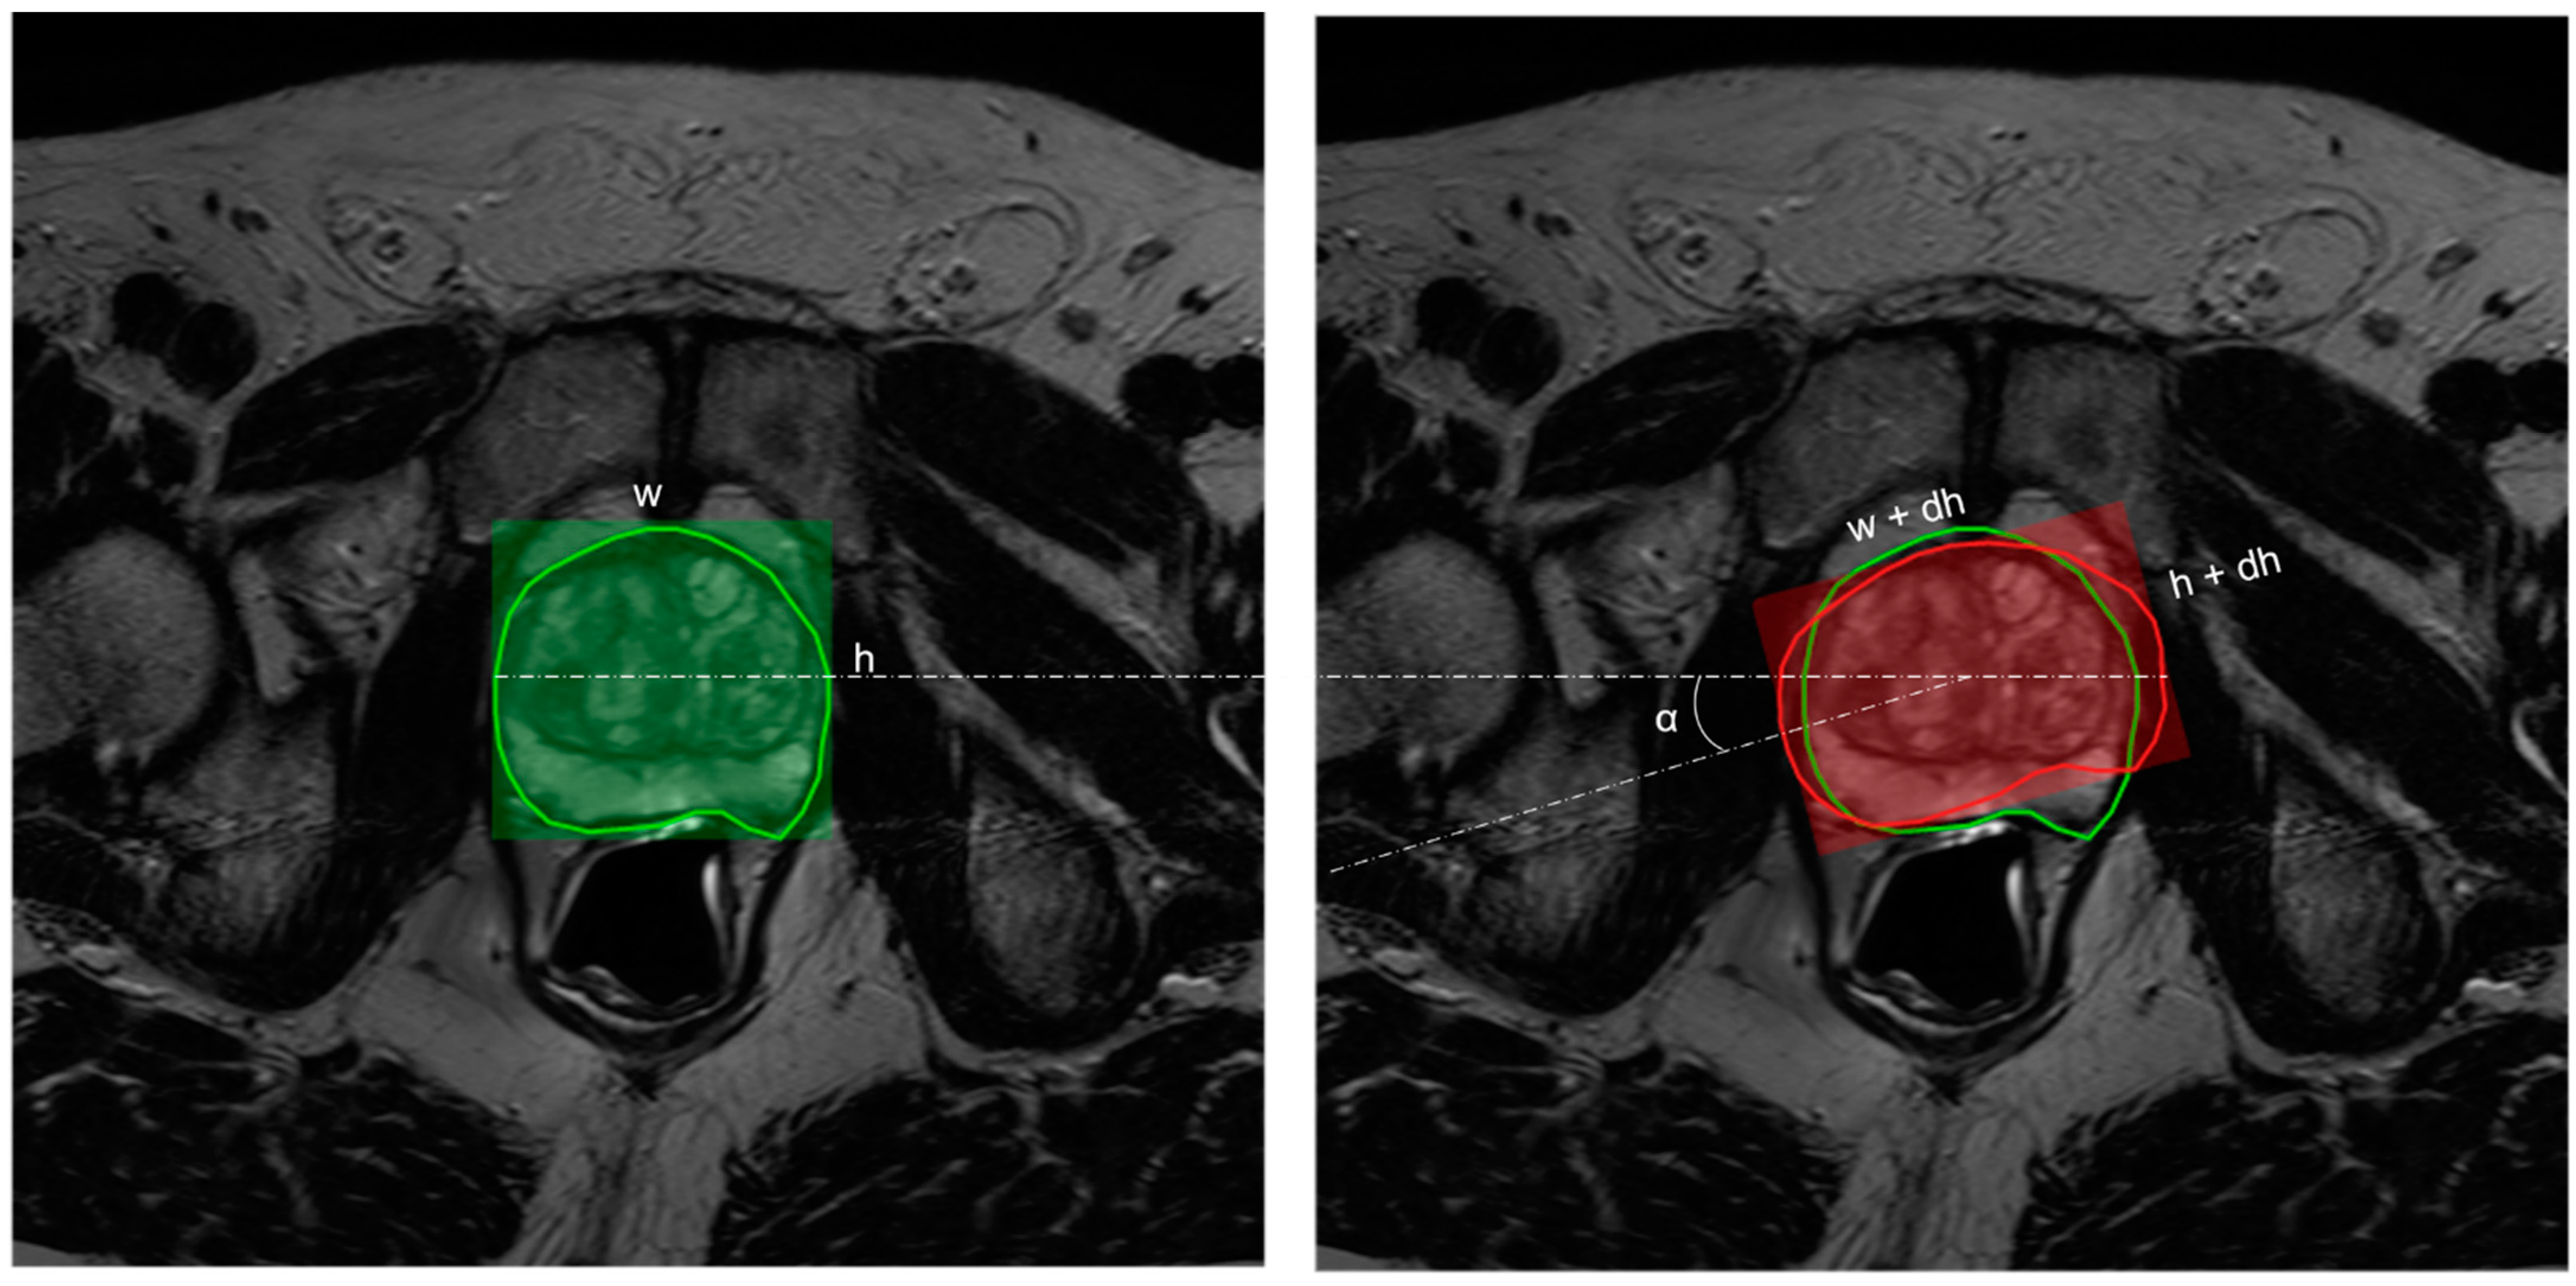

Figure 2.

Illustration of in-plane augmentation. The width, w, and height, h, associated with the contour drawn by the radiologist (left in green) in the axial plane are allowed to undergo random perturbation by a delta value—dw, dh ~ U (−2.7 mm, 2.7 mm). This results in a transformed contour (right in red) with width, w’ = w + dw, and height, h’ = h + dh. In addition to this, the contour is also allowed to randomly rotate in the z-axis at an angle, α ~ U(−5°, +5°).

As the name suggests, in-plane augmentation essentially simulates the variability in contouring within the axial plane (i.e., variations within X and Y dimensions associated with a slice). Here the prostate contours are allowed to have variations in their latero-lateral or antero-posterior dimensions by a value randomly sampled from a uniform distribution within the interval [−2.7 mm, +2.7 mm]. In addition to this, the contour is randomly allowed to rotate around the z-axis at a small angle, α ~ U(−5°, +5°) (see Figure 2). The choice of intervals for contour variability [−2.7 mm, +2.7 mm] was established by following the results of studies on the inter-observer variability in prostate contouring using MRI [49,50]. These studies report an average standard deviation of 1.1 mm, corresponding to 2.7 mm at a 95% confidence interval.